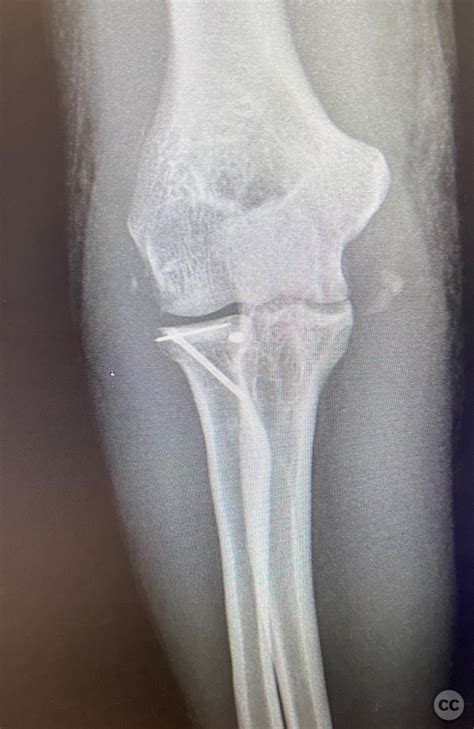

Diagnosing the displacement of fractures involves a combination of clinical examination and imaging studies. The diagnostic process typically includes:

• Clinical examination: A thorough physical examination to assess the extent of the injury and any associated symptoms.

• Imaging studies: X-rays, CT scans, or MRI scans to visualize the fracture and determine the degree and direction of displacement.

• Surgical treatment: In cases of severe displacement, surgery may be required to realign the bone fragments and stabilize the fracture. Surgical options include:

• Open reduction and internal fixation (ORIF): This involves surgically realigning the bone fragments and using plates, screws, or rods to hold them in place.

• Closed reduction and percutaneous pinning: This involves manipulating the bone fragments back into place without surgery and using pins or wires to hold them in position.